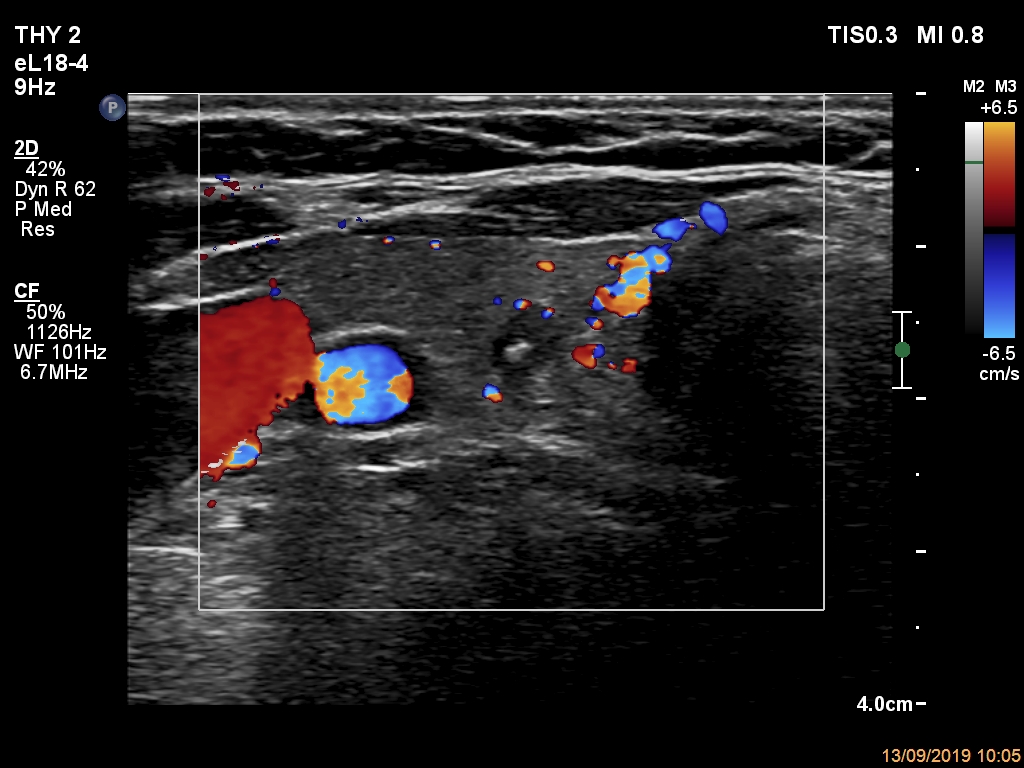

Ultrasonography. The thyroid was echonormal. There was a small hypoechogenic lesion in the central part of the right lobe. The lesion had microcalcification and non-parallel orientation, presented both taller-than-wide and taller-than-long shape. The left lobe had a hypoechogenic mass composed of discrete lesions. The whole mass displayed undulated margins which corresponded to non-pathological lobulation. On the other hand, a lesion within the mass had pathological, spiculated margins.

Comment. This case illustrates the difference between pathological and non-pathological forms of lobulation.